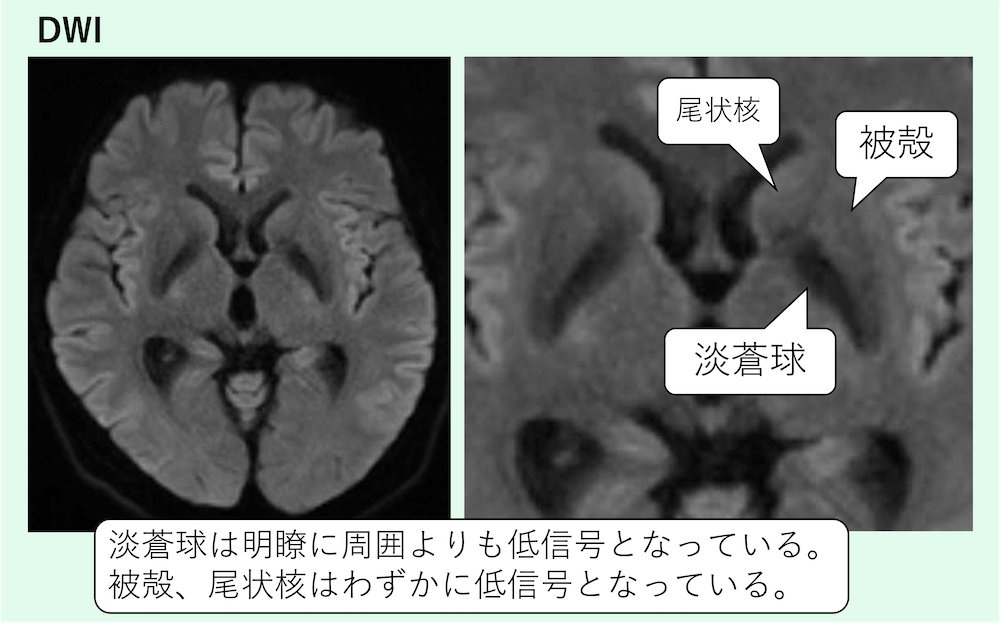

症例 70歳代男性

淡蒼球は明瞭に周囲よりも低信号となっています。

被殻、尾状核はわずかに低信号となっています。